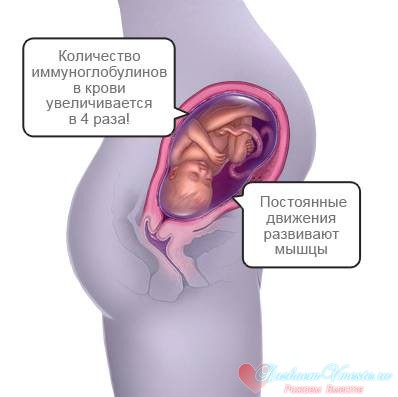

Мозок дитини продовжує активно розвиватися, навколо волокон, а особливо нервових, постійно утворюються нові оболонки. Малюк вже стає здатний до навчання. Він починає реагувати на світло і на темряву, його очі формуються, а зіниці поступово набувають остаточну форму.

Малюк в цей період дуже активний, він час від часу обов'язково штовхає. Найбільш характерні руху дитини в цей період - здригання і ворушіння кінцівками, це показує, що він розвивається нормально.